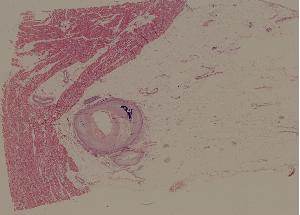

44. Arteriolosclerosis of kidney